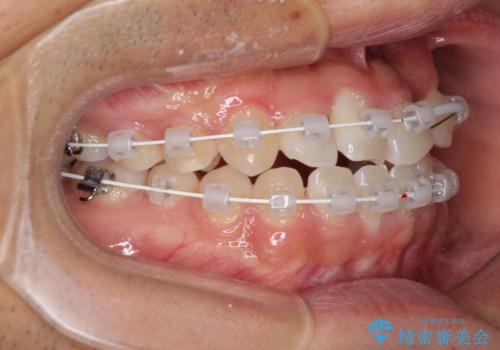

- 矯正装置

- 審美装置

治療期間を極力短くしたいとのことで、ワイヤー矯正により治療を行うこととしました。